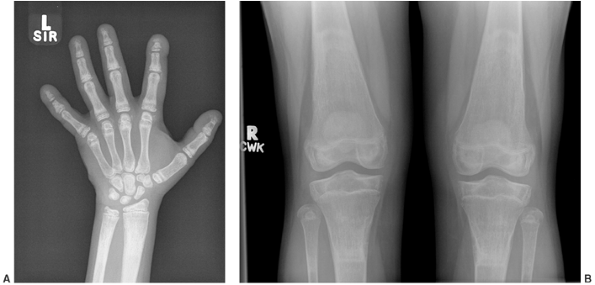

![]() |

Figure 7.6 Renal osteodystrophy in an 8-year-old boy. A:

Radiographs of the hand show sclerosis, acroosteolysis, and soft tissue calcification around the metacarpal phalangeal (MCP) and proximal interphalangeal (PIP) joints. B: Radiographs of the knees show subperiosteal resorption at the medial border of the proximal tibia. |